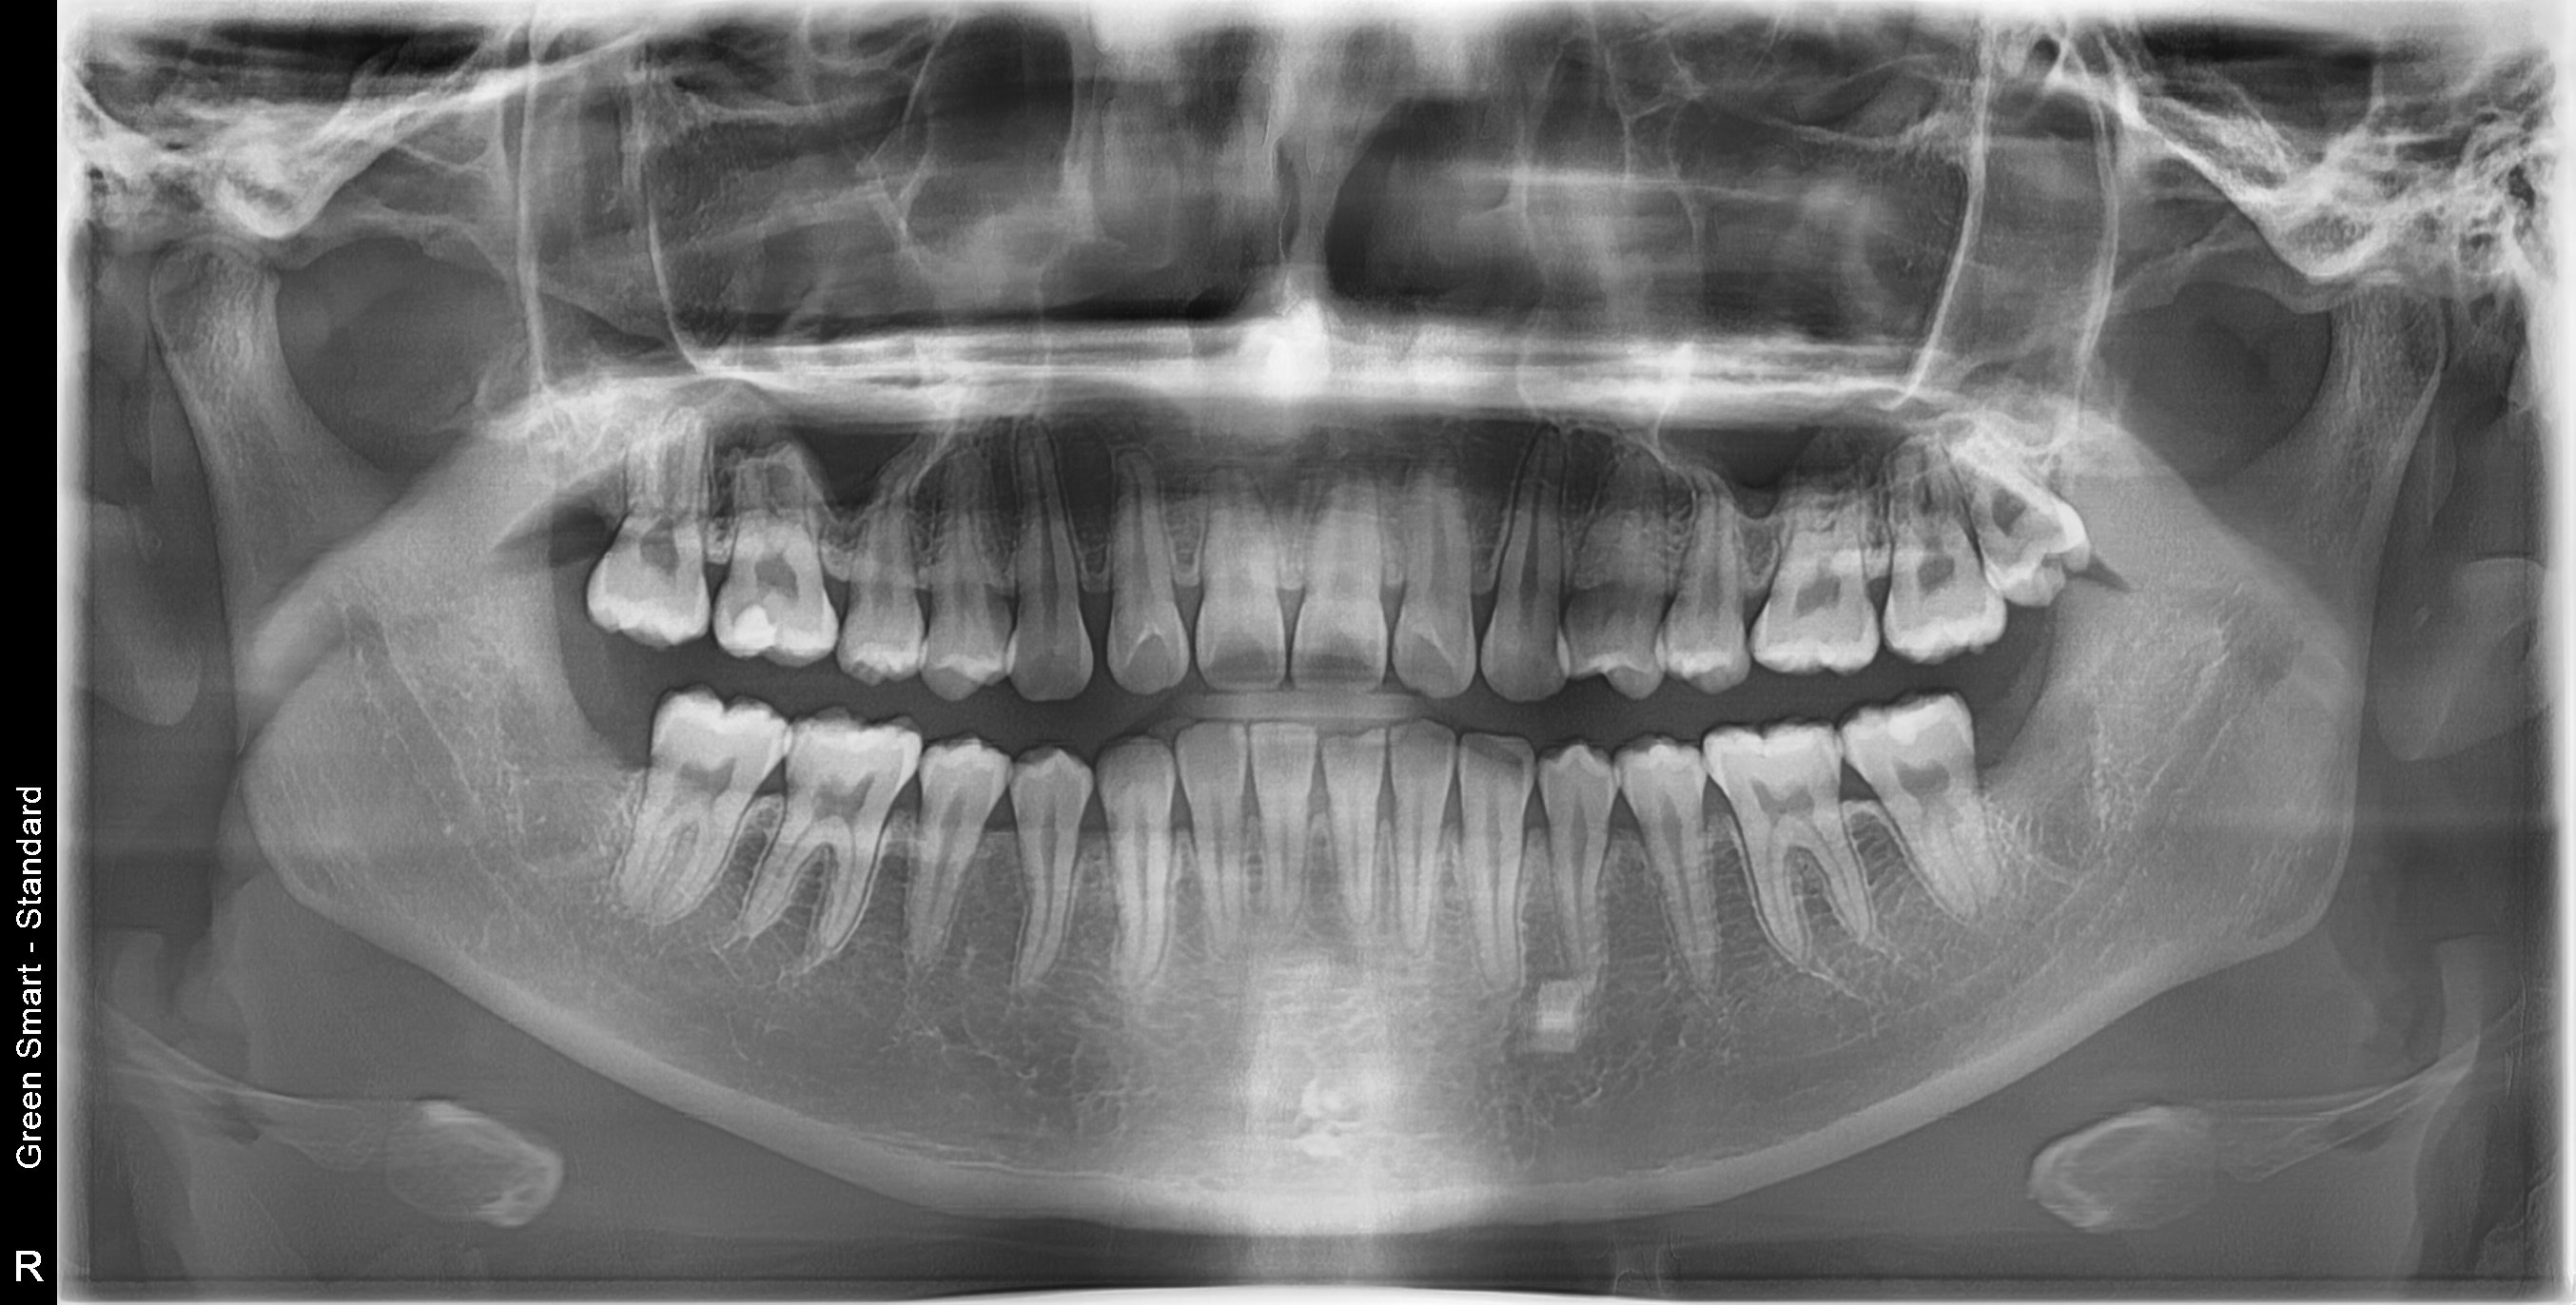

누운 사랑니

옆으로 누워 자라며 옆 치아를 압박할 수 있습니다

염증 발생

방치된 사랑니로 인해 잇몸이 붓고 염증이 생길 수 있습니다

복잡한 매복 사랑니 - 잇몸 속 깊이 묻혀있어도 OK

신경 근접 사랑니 - 신경 손상 걱정 없는 안전한 발치

수평 매복 사랑니 - 옆으로 누워있는 어려운 케이스도 가능